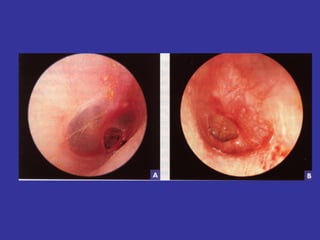

Erythematous,  opaque, bulging TM Light reflex is reduced, landmarks gone Air and fluids bubbles  TM bulging with a  yellow purulent  effusion

On the left, an endoscopic view of the throat shows almost complete blockage of the airway (arrow). This finding is typical of epiglottitis.  On the right, the airway has been opened (arrow) after insertion and removal of an endotracheal tube, although some redness and blood remain

Erythematous, opaque,bulging TM Light reflex is reduced, landmarks gone Air and fluids bubbles TM bulging with a yellow purulent effusion

On the left,an endoscopic view of the throat shows almost complete blockage of the airway (arrow). This finding is typical of epiglottitis. On the right, the airway has been opened (arrow) after insertion and removal of an endotracheal tube, although some redness and blood remain